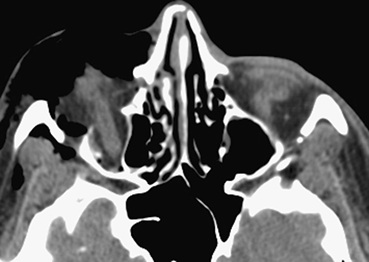

Figure 14.2.1: Axial soft tissue window of inferior orbit shows abnormality, which is difficult to assess using this window.

Figure 14.2.2: Coronal soft tissue window shows a large blowout fracture of the right orbital floor.

This finding was missed on the axial study in Figure 14.2.1, demonstrating the importance of reviewing both axial and coronal images.